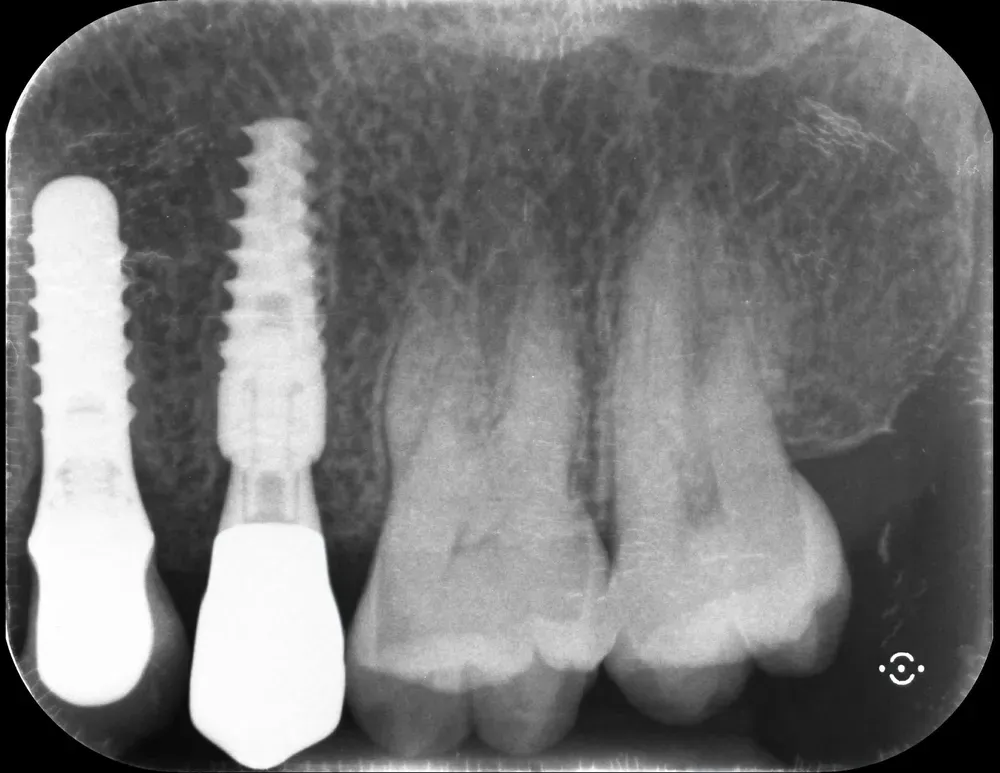

La regola dei 4mm di Linkevičius ci viene in aiuto per stabilire la posizione verticale che protegge l’impianto dal riassorbimento osseo, sempre nel caso di connessioni affidabili dal punto di vista batteriologico. Nelle prossime immagini, dei monconi protesici relativamente lunghi su impianti a connessione conica, testimoniano l’ottimo risultato reale di questo concetto, con impianti perfettamente integrati e privi di infiltrazione infiammatoria, anche in condizioni ossee impegnative.

Per concludere il confronto tra le varie connessioni, l’immagine che segue è una radiografia con due impianti affiancati: un tissue-level ben posizionato fatto da un collega anni addietro e un impianto a connessione conica in posizione infracrestale con abutment della corretta lunghezza per il caso. Il secondo è un mio caso. È interessante notare come il cono dello spazio biologico sia identico. Se ben posizionati, tutti gli impianti funzionano egregiamente (l’impianto più vecchio inizia a soffrire un pochino, ma questa è un’altra storia).